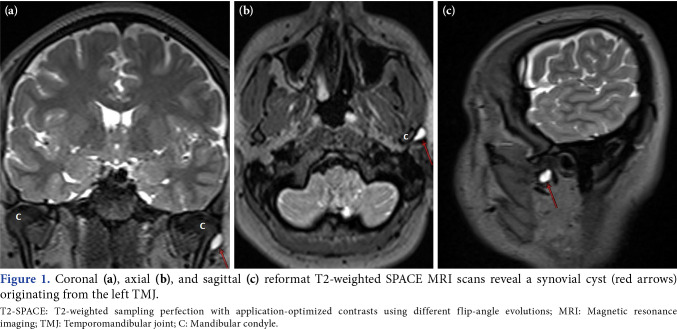

Results: At least one incidental finding was detected in the TMJ in 37.1% (n=185) of the patients included in our study. In our study, the most common (13.6%) MRI findings were osteoarthritic changes and synovial cysts. Joint effusion (13.2%) and disc displacement (9%) were less frequent. When the relationship between the age of the patients and the presence of incidental findings, degeneration, effusion, disc displacement, and cyst was examined, the age of the patients with incidental findings (p=0.001) and osteoarthritic changes (p<0.001) was statistically significantly higher.

Conclusion: Incidental findings, particularly osteoarthritic changes and synovial cysts, can be seen quite commonly in the TMJ in brain MRI using 3D T2-SPACE sequences in the general population. The 3D T2-SPACE sequence provides valuable information in the recognition of TMJ disorders.